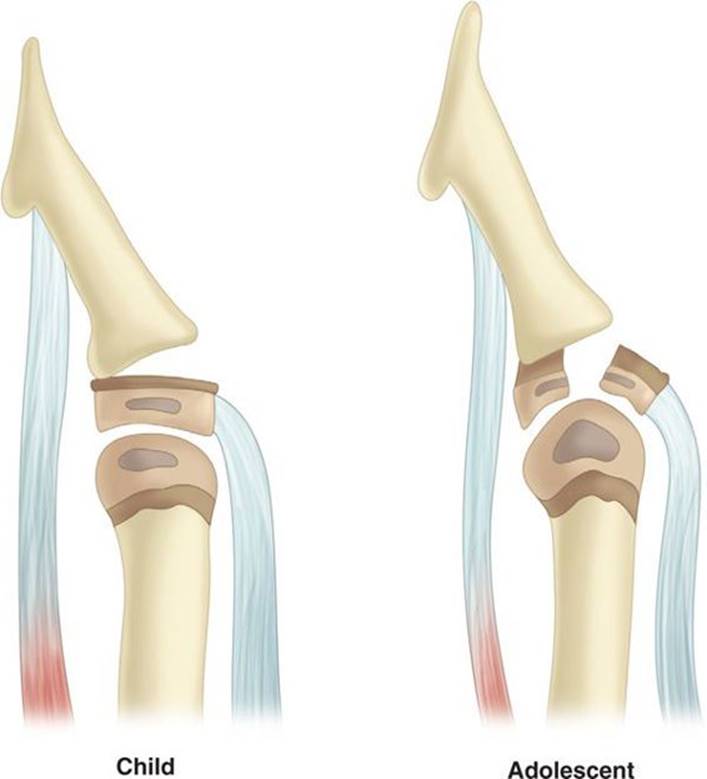

A hyperflexion force applied to the tip of the finger may result in one of two types of pediatric injuries (Fig. 30-14). In the preadolescent, a Salter–Harris type I or II fracture occurs with a mallet deformity which is the result of an avulsion of the extensor tendon from the base of the distal phalanx. If a child has a mallet finger and inability to extend the distal phalanx, this injury should be assumed even if a fracture cannot be identified on radiographs. In the adolescent hyperflexion injury, a displaced Salter–Harris type III fracture occurs. These injuries are treated by wound care, closed reduction, and splinting in slight hyperextension. If adequate reduction is not obtained, then open reduction and Kirschner-wire fixation is performed.26

FIGURE 30-14. Mallet injuries are caused by avulsion of the extensor tendon from the distal phalanx or from a fracture of the dorsal base of the distal phalanx. An extension lag at the DIP joint is present, and the patient is unable to actively extend the DIP joint. In children, a Salter–Harris type I or II fracture is seen. In the adolescent, a Salter–Harris type III fracture occurs. These fractures may be difficult to detect radiographically because the epiphysis is not fully ossified in children. Inability to actively extend the DIP joint and a mallet deformity reveal the extent of injury.